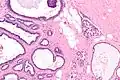

| Micrograph of collagenous spherulosis with the characteristic histomorphology - intratubular eosinophilic material with a spoke-like arrangement. H&E stain. | |

Collagenous spherulosis is characterized by a tubular/cribriform architecture with intratubular eosinophilic material that classically is arranged like the spokes of a wheel ("radial spikes"). There is usually no mitotic activity, and two cells populations (epithelial & myoepithelial) are present, like in benign breast glands.

The lesions are typically small (less than 50 spherules per lesion, less than 100 micrometers in size) and may be multifocal.